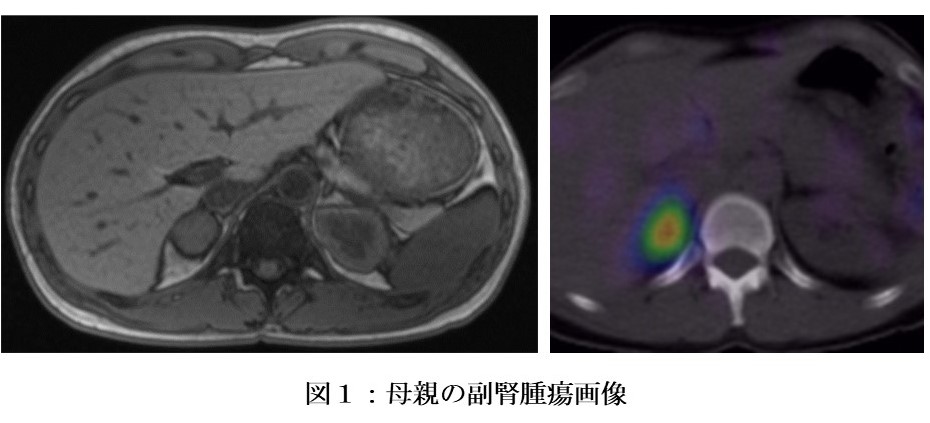

「11oxC19s」は、副腎で産生され、不活性化されずに胎盤を通過します。この児の母親は副腎腫瘍を有しており(図1)、血中「11oxC19s」が高値、一方「テストステロン」と「アンドロステンジオン」は正常範囲内でした。「11oxC19s」の値は腫瘍除去後に正常化しました。